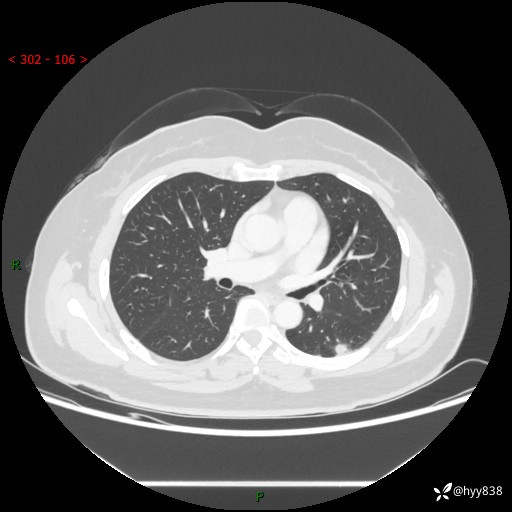

胸部CT平扫(2023.3)